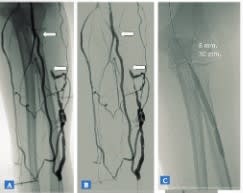

La acumulación casuística después de asistir a más de 20.000 pacientes relacionados con la hemodiálisis (procedimientos en la sala de angiografía, ecografías, mapas vasculares, tratamientos combinados fluoroscopia-ecografía, contrastes alternativos como el CO2, nuevos balones para fístulas - balones cortantes, crioplastia, balón con droga, etcétera), nos animó a plasmar esa experiencia en un libro que pudiera condensar los casos más representativos en la práctica diaria de cualquier radiólogo vascular dedicado al acceso vascular de hemodiálisis. De esta forma, hemos hecho un esfuerzo por imaginarnos a nuestros colegas en su día a día enfrentándose a este campo tan apasionante del vascular intervencionismo. Para ello, hemos planteado este libro con un formato que ayude al especialista a entender cómo tiene que enfocar cada caso desde las esquinas de la clínica, la técnica y el protocolo de actuación; es decir, tal como nosotros mismos venimos haciéndolo diariamente.

Cada caso viene presentado como si fuese una historia clínica, con su motivo de consulta y sus antecedentes personales, especialmente los referidos a los accesos vasculares de hemodiálisis, seguido de una exploración física. Se acompaña de un informe del procedimiento realizado con la técnica empleada y los abordajes, así como los balones de angioplastia y/o stents utilizados. Para finalizar, escribimos unos comentarios sobre el procedimiento realizado y todo caso va acompañado de un gran número de imágenes explicativas de alta calidad